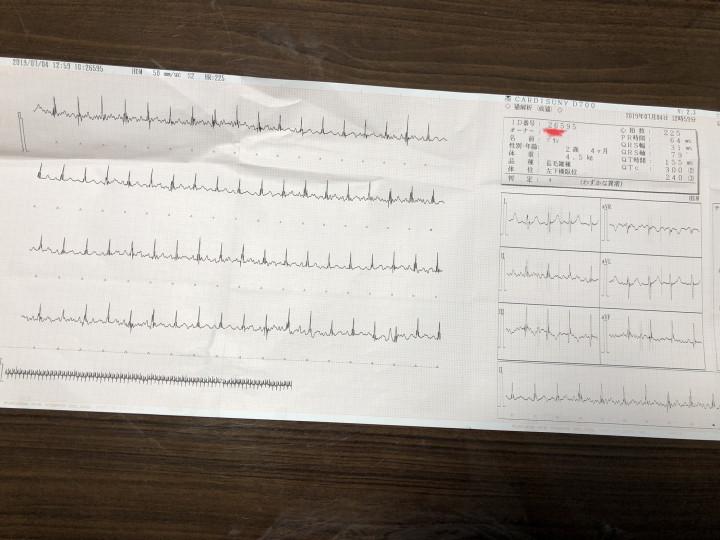

心電図取りました。

不整脈は出ていません。

心筋の厚さも基準値内でした。

コレも確認してください。特に

今のところ問題はないようです。